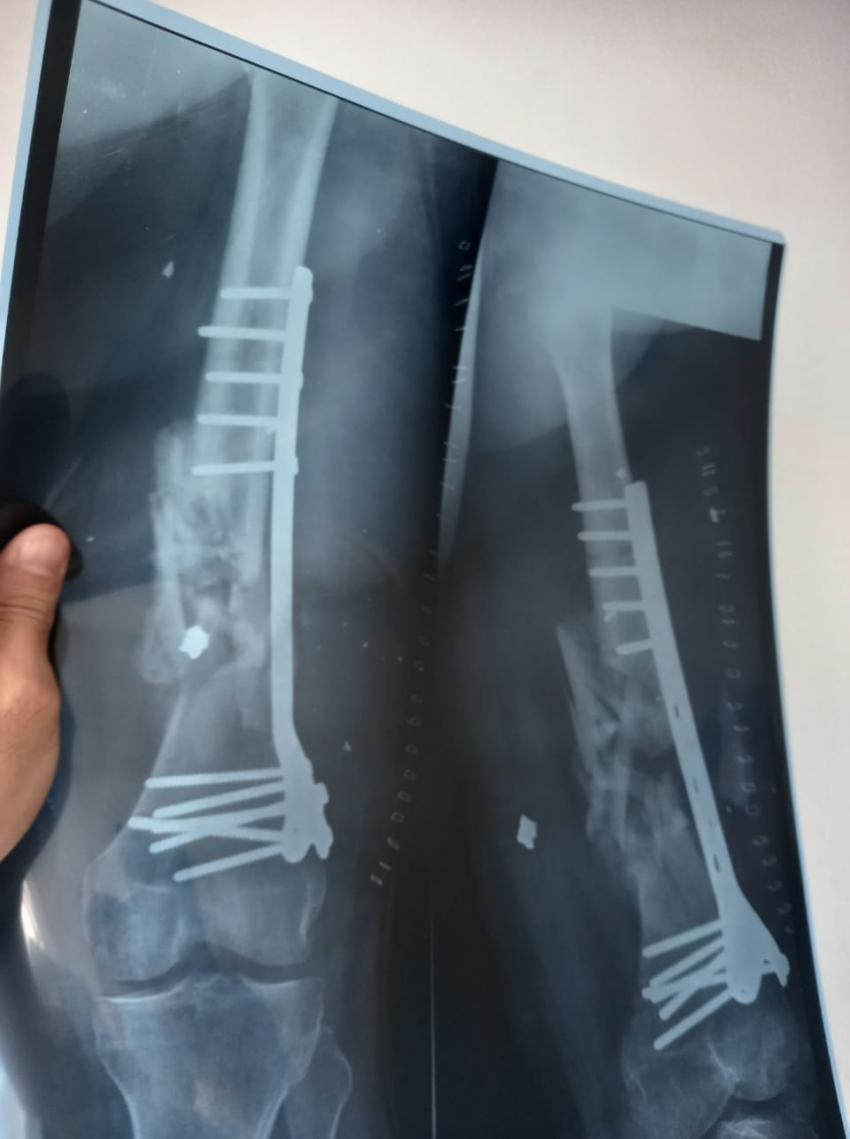

المستشفى الميداني غزة /78 يجري عملية جراحية نوعية

في إطار الجهود التي يقدمها المستشفى من أجل تقديم الخدمة والرعاية الطبية والإنسانية للأهل في قطاع غزة، أجرت طواقم المستشفى الميداني الأردني غزة /78 أمس السبت، عملية جراحية لتثبيت كسر مفتوح في أسفل عظم الفخذ (DISTAL FEMUR FX ORIF).

وقال قائد قوة المستشفى، إن العملية قام بها فريق طبي متخصص من جراحي العظام والمفاصل والتخدير من كوادر المستشفى الميداني الأردني غزة /78، مضيفاً أن المستشفى تعامل مع 5064 حالة مختلفة خلال الشهر الحالي من بينها إجراء 31 عملية كبرى و4 عمليات صغرى إضافة لحالة ولادة.

من جانبه بين طبيب جراحة العظام والمفاصل أن المريض كان يعاني من كسر مفتوح في أسفل عظم الفخذ اليمين مما أدى إلى تفتت العظم وتهتك الأنسجة المحيطة به نتيجة الإصابة التي تعرض لها المريض، وتم إجراء عملية جراحية وتركيب صفيحة معدنية وبراغي وإزالة المثبت الخارجي في المستشفى الميداني الأردني لكونه المستشفى الوحيد الذي ما زال مستمراً شمال القطاع.

وعبر ذوو المريض عن بالغ شكرهم وتقديرهم الملك عبدالله الثاني مثمنين الجهود الكبيرة التي تقوم بها طواقم المستشفى الميداني الأردني في التخفيف من أثار الحرب التي يتعرض لها السكان المدنيين في القطاع.